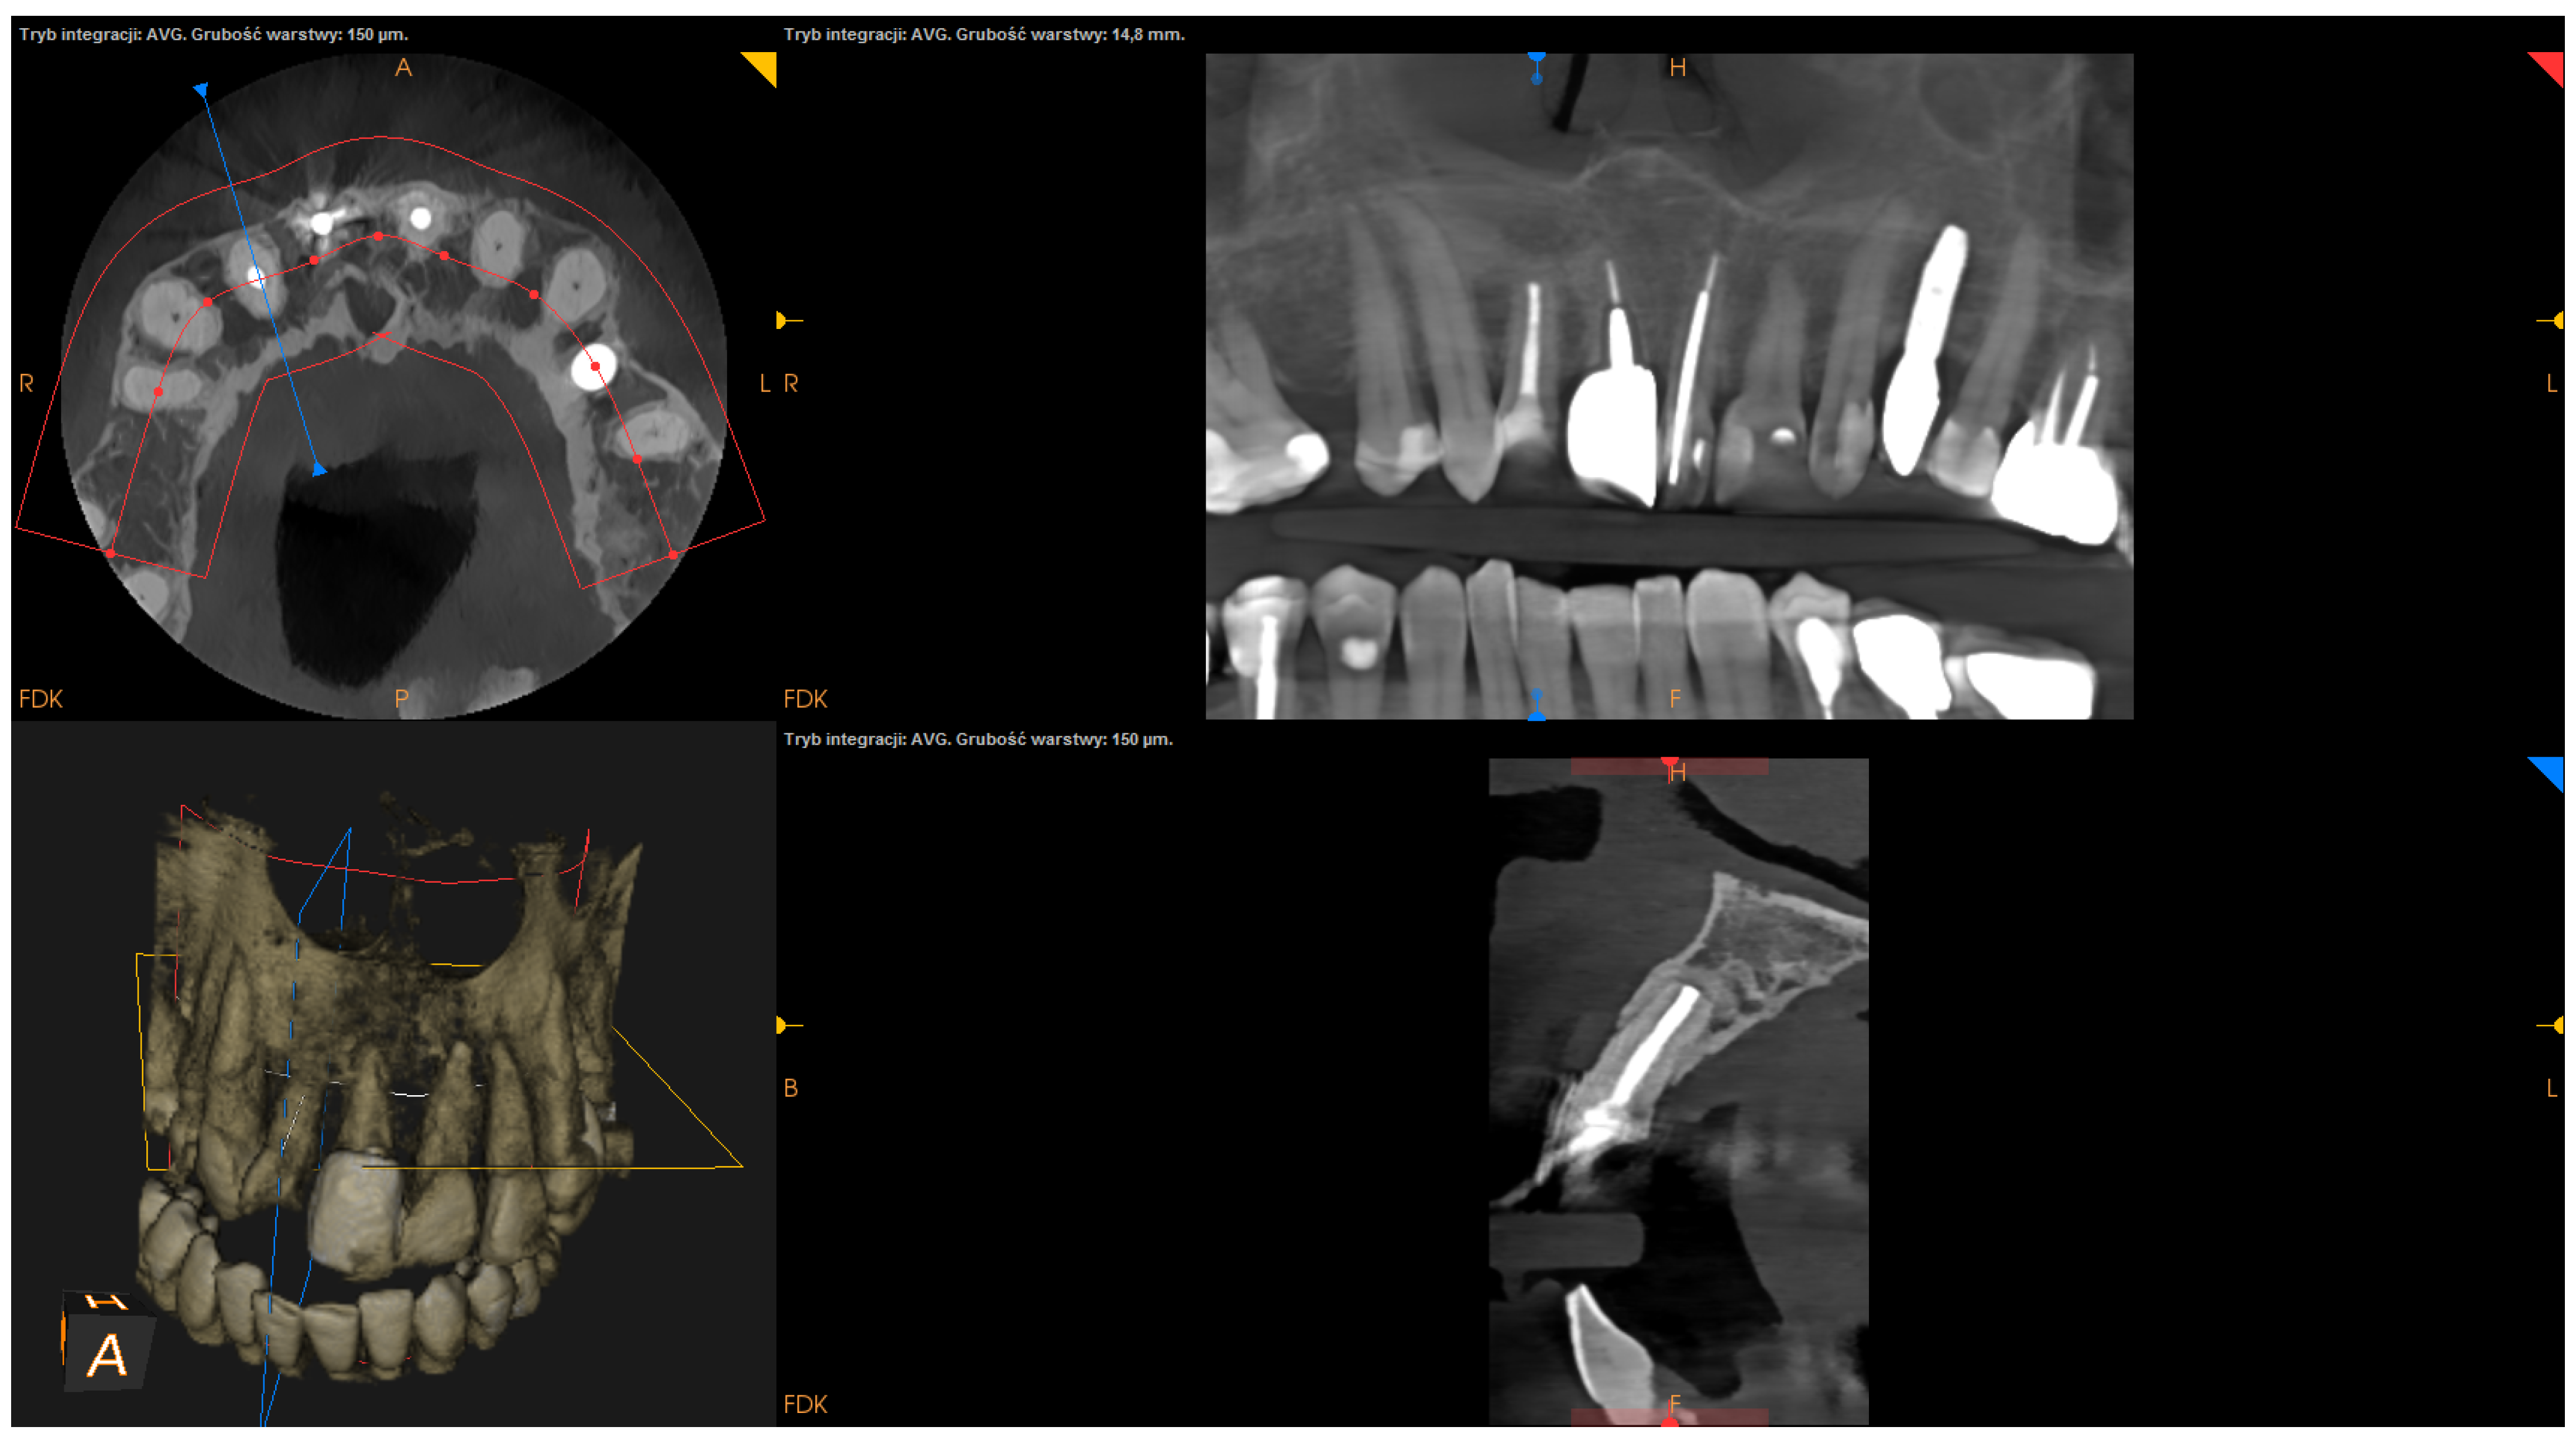

- The status of radiographic healing (rated in all sections, according to modified PENN 3D criteria [28]) was classified as complete healing (Figure 1), incomplete healing (Figure 2), uncertain healing (Figure 3), or unsatisfactory healing (Figure 4).

Figure 1. CBCT image (CS 8100 3D Carestream Dentalⓡ) example of complete healing based on PENN 3D criteria. Non-English annotations present software technicalities (AVG integration mode and layer thickness).